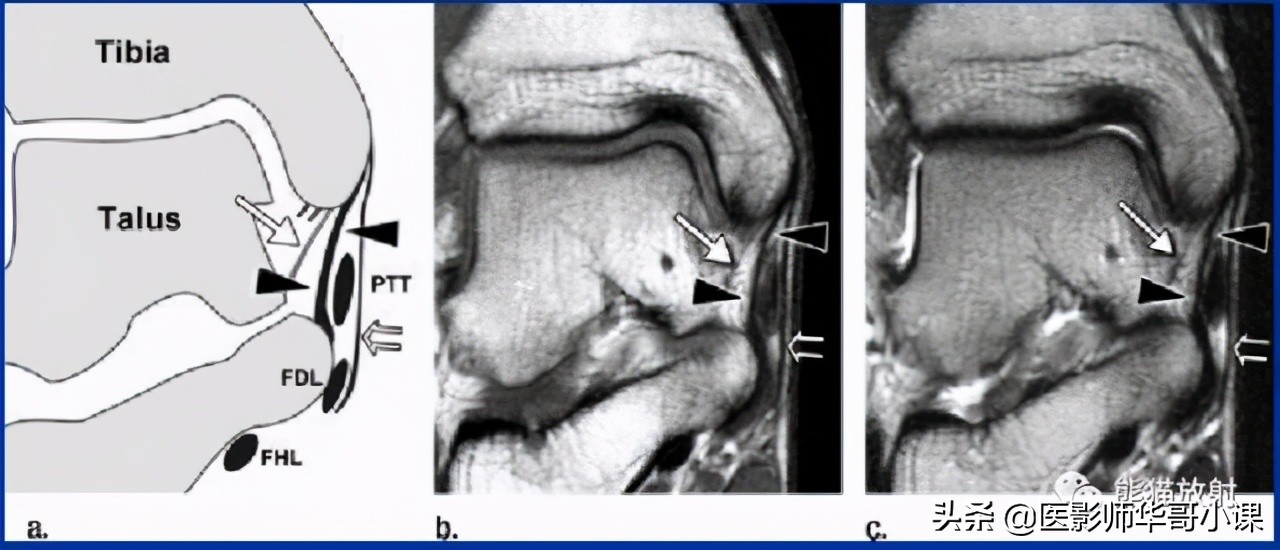

三角韧带与踝关节其他结构共同维持踝关节稳定。三角韧带属于复合韧带,呈扇形结构,由浅层和深层组成。

包括: 胫距韧带(前/后)、胫跟韧带、胫舟韧带 。

↓ 胫距后韧带损伤